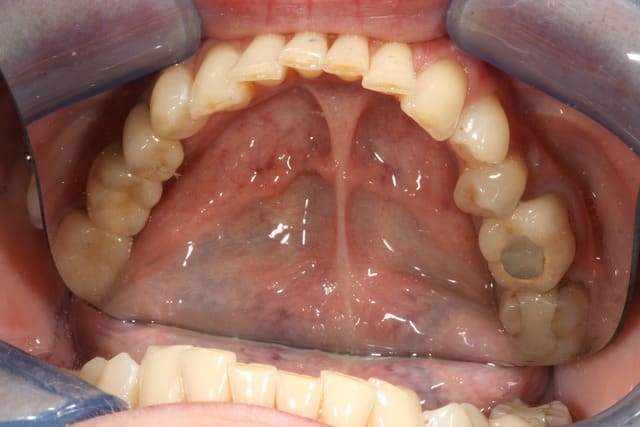

voilà le resultat collé

je suis resté trop supragingival, mais la patiente est très contente (ouf, c'est l'essentiel !)

Occlusal jyrk8g - Eugenol

Zooom bjj8ay - Eugenol